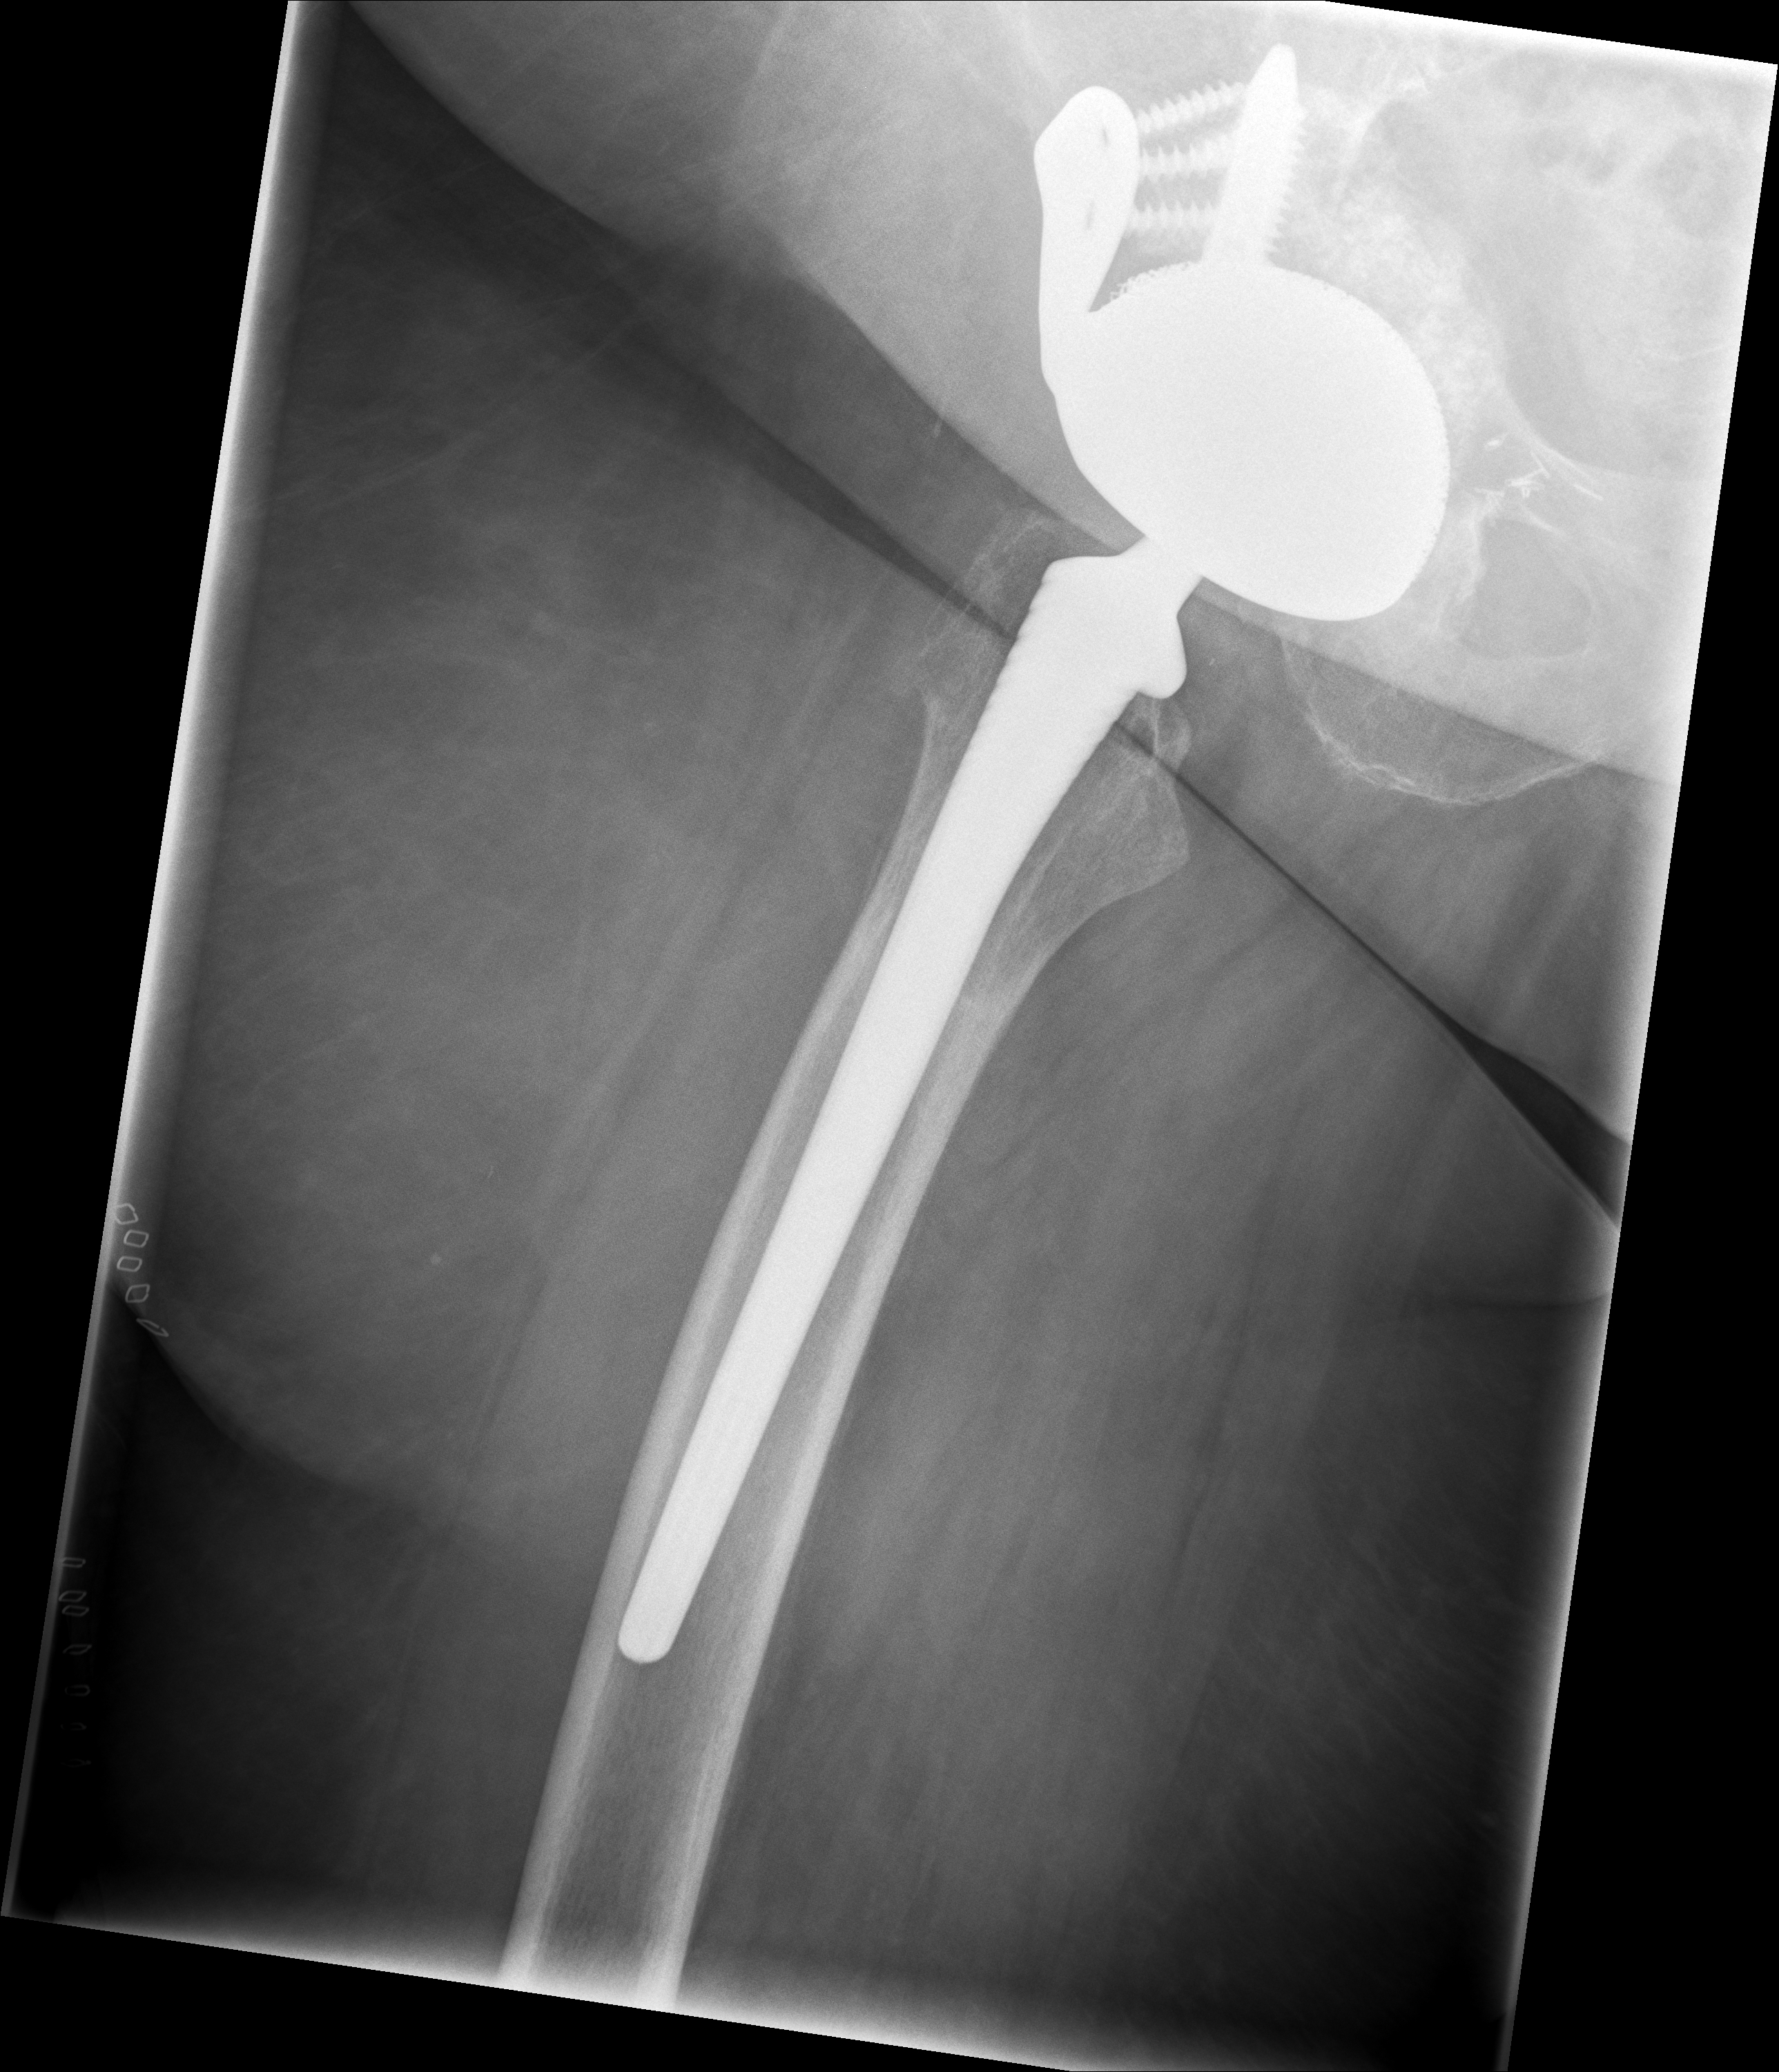

Röntgenbilder im Verlauf: korrekte Lage → Luxation → neue TEP nach Wiedereinbau

24.02.2026 - Neue TEP

Röntgen Februar 2026

Neue Hüft-TEP rechts nach Wiedereinbau

24.02.2026 - Neue TEP!

Becken 2026

24.02.2026 - Postoperativ

Röntgen Becken + Hüfte rechts (Kontrolle nach Wiedereinbau)

3 Aufnahmen | Becken tief + 2x Hüfte Lauenstein | 5 Tage nach OP

24. Februar 2026

Postoperative Röntgenkontrolle

Röntgen Becken tief + 2x Hüfte Lauenstein R – Kontrolle 5 Tage nach Wiedereinbau.

24.02.2026 - POSTOP

Röntgen Becken tief (nach Wiedereinbau)

DICOM

Kontrolle Becken 5 Tage nach Wiedereinbau TEP

Röntgen Hüfte Lauenstein R (1)

Kontrolle Hüfte 5 Tage nach Wiedereinbau TEP

Röntgen Hüfte Lauenstein R (2)